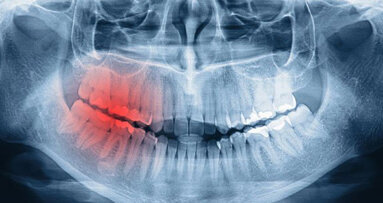

Eine neue Beobachtungsstudie geht den Gründen von Implantatverlusten nach. © didesign021 - shutterstock.com

FRANKFURT AM MAIN - Eine neue Beobachtungsstudie gibt Aufschluss über Gründe von Misserfolgen bei der Versorgung von Patienten mit "künstlichen Wurzeln".